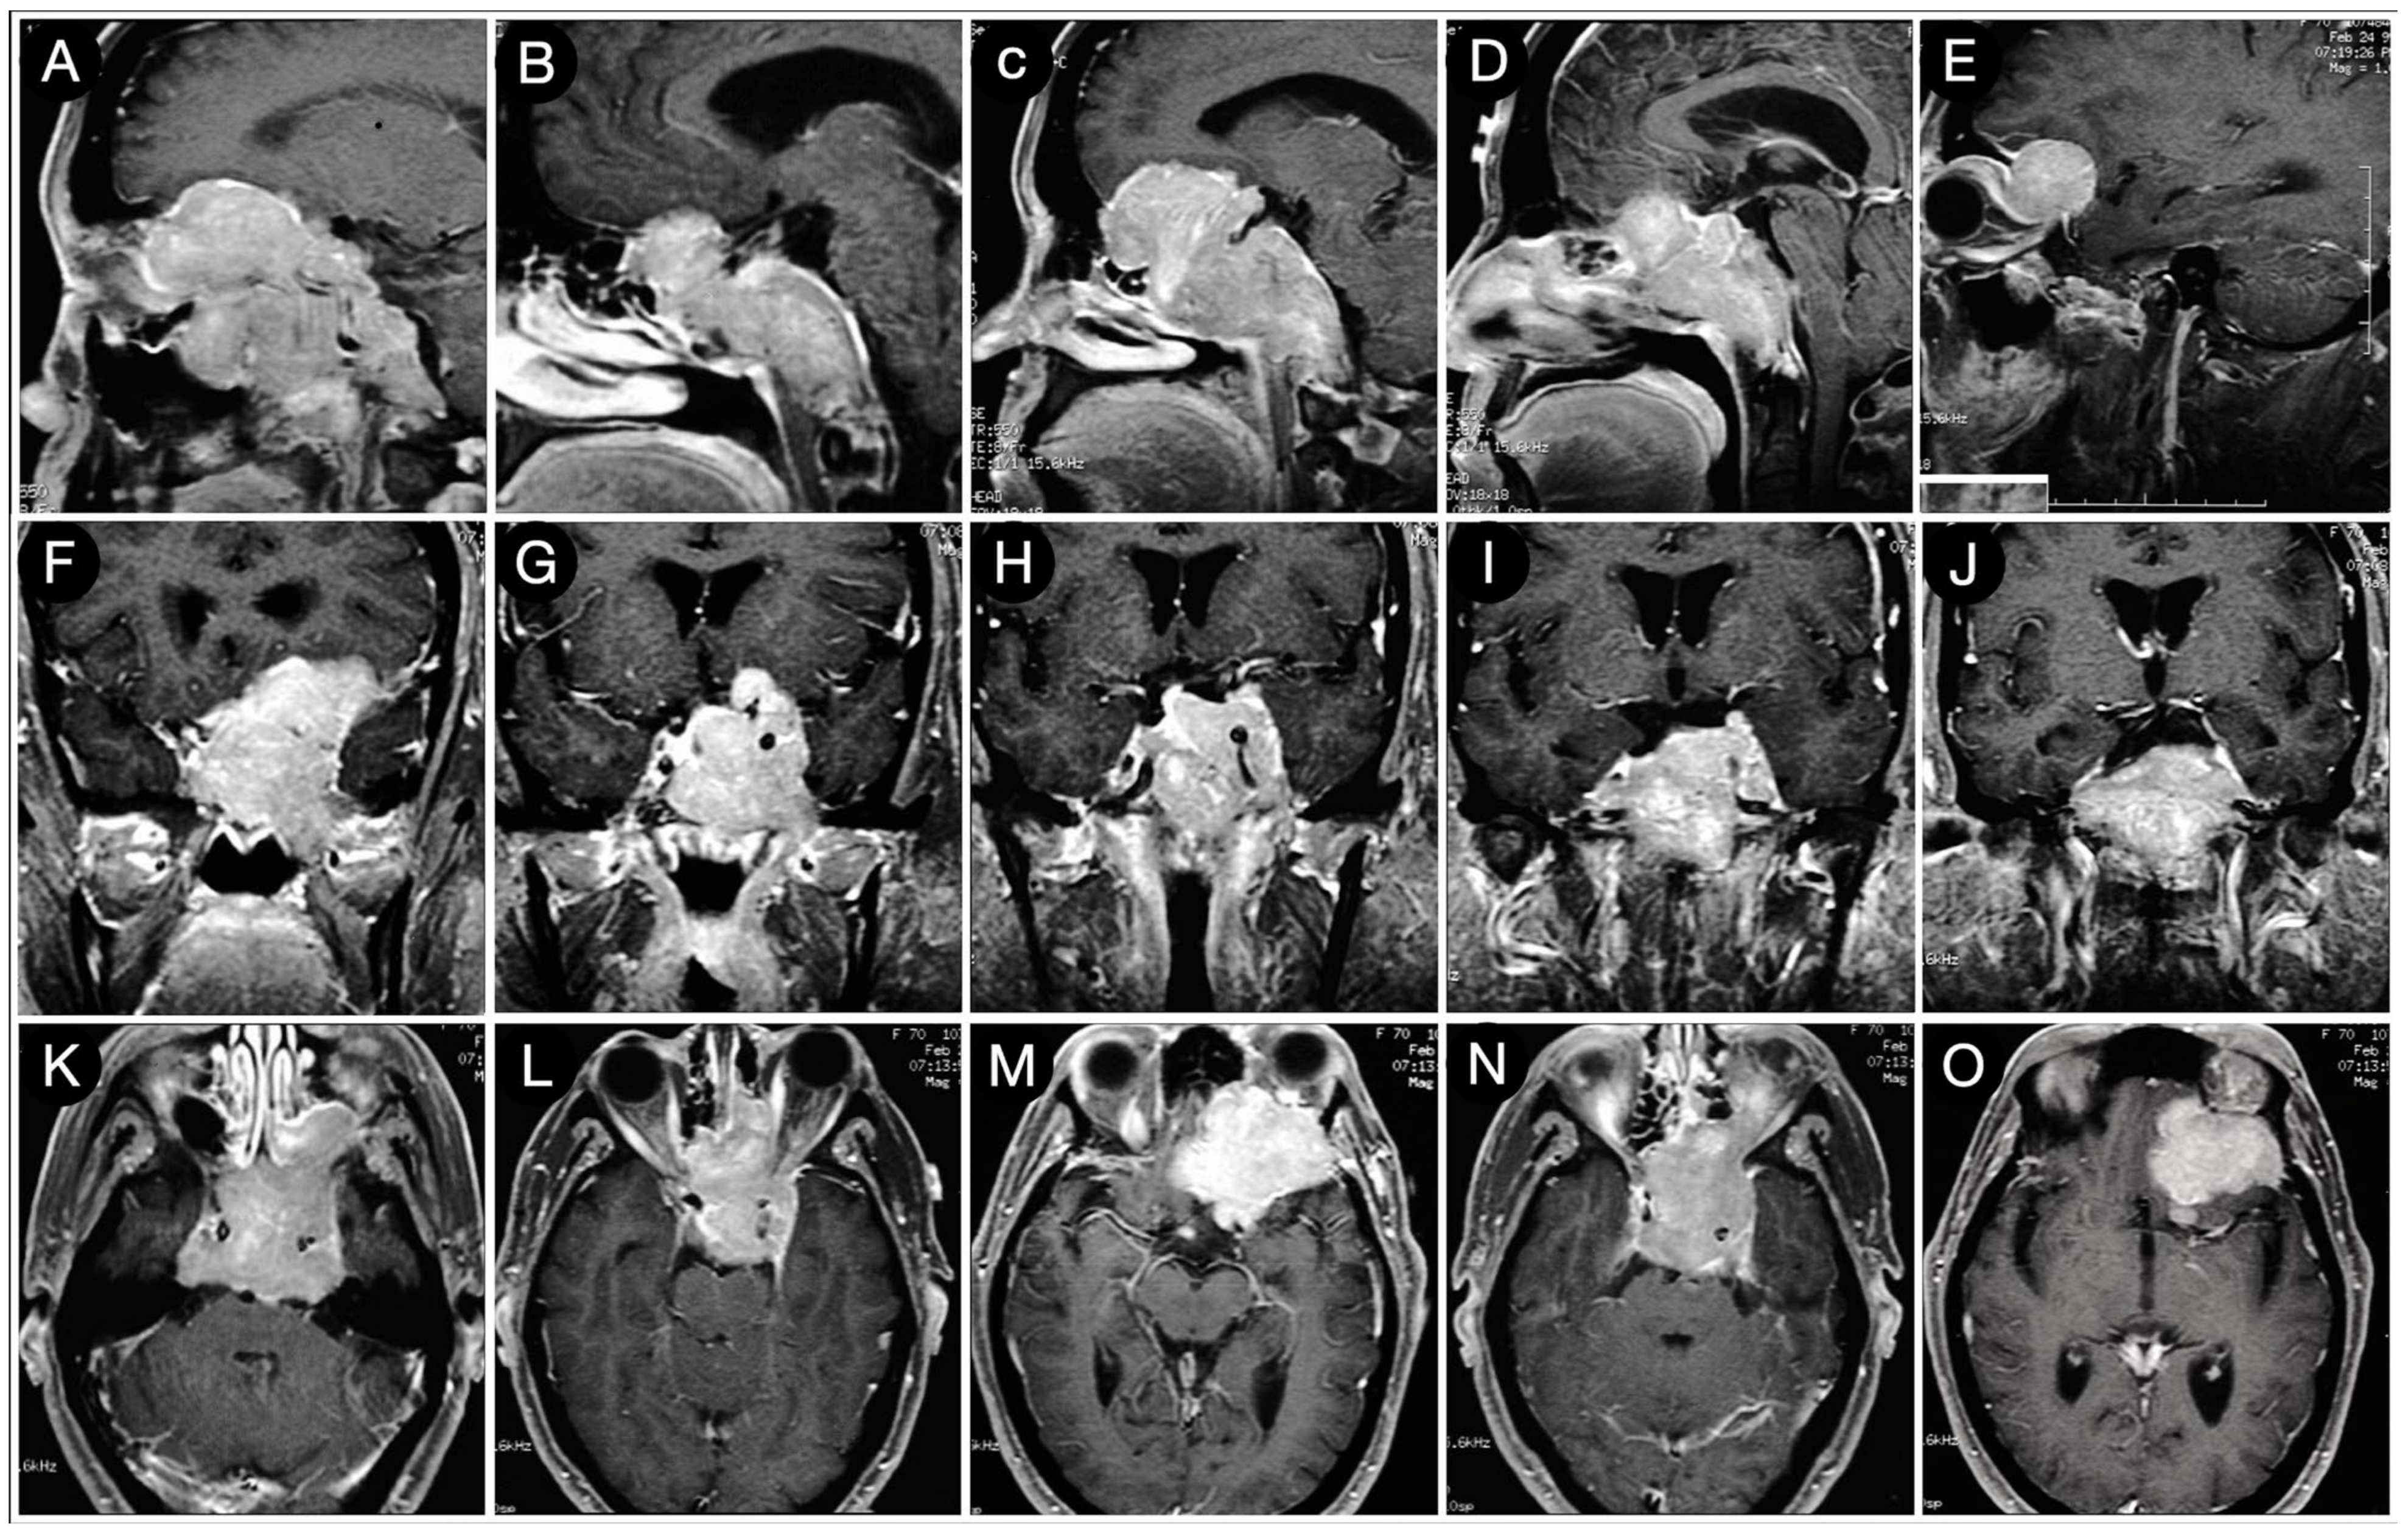

3.2.1. Case #2: Involvement of the Anterior Skull Base

3.2.2. Case #3: Paramedian Pattern of Growth with Parenchymal Invasion

3.3.1. Case #4: Involvement of the Middle Skull Base with Parenchymal Invasion

3.3.2. Case #5: Extension beyond the Lateral Wall of the Cavernous Sinus

3.3.3. Case #6: Encasement of the Posterior Communicating and Anterior Choroidal Artery

Case #7: Encasement of the Paraclinoid and Supraclinoid Internal Carotid Artery

Case #8: Aggressive ACTH Tumor with Multiple Recurrences